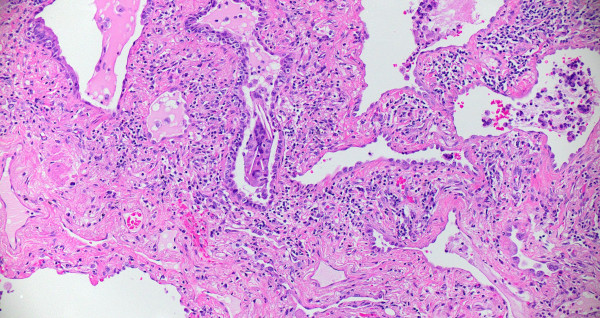

Compute tomography (CT) scan of the chest showed subpleural and peribronchial fibrosis with air-trapping on expiratory phase. The findings were read as likely “non-IPF pattern.” A serum antibody panel for hypersensitivity pneumonitis was positive for antibodies to Aspergillus flavus. Histologic sections of her lung biopsy demonstrated airways with peribronchiolar fibrosis with extensive metaplastic changes (Figure 1). Intra-alveolar giant cells and histiocytes with cholesterol clefts were seen (Figures 2-3). There were areas of interstitial inflammation and fibrosis resembling a cellular non-specific interstitial pneumonia (NSIP) pattern of injury (Figure 4). Also seen were extensive peribronchiolar metaplasia, microscopic “honeycombing”, interstitial giant cells, and poorly-formed granulomata (Figures 5-7).